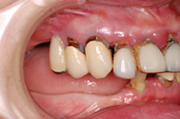

審美的で健康にも良い セラミックスでの治療はこんな感じです。 |

残念ながら、2次カリエスになってしまってます

セメントは唾液中の酸によって時間の経過と共に溶かされてしまうのです。

セメントが溶けだして、かぶせ物が取れてしまうだけならまだ良いのです。

しかし、溶け出して、空いたスペースにプラーク(歯垢)が入り込んでしまい、かぶせ物の下にある歯を再び、虫歯にしてしまうのです。これを2次カリエスといいます。